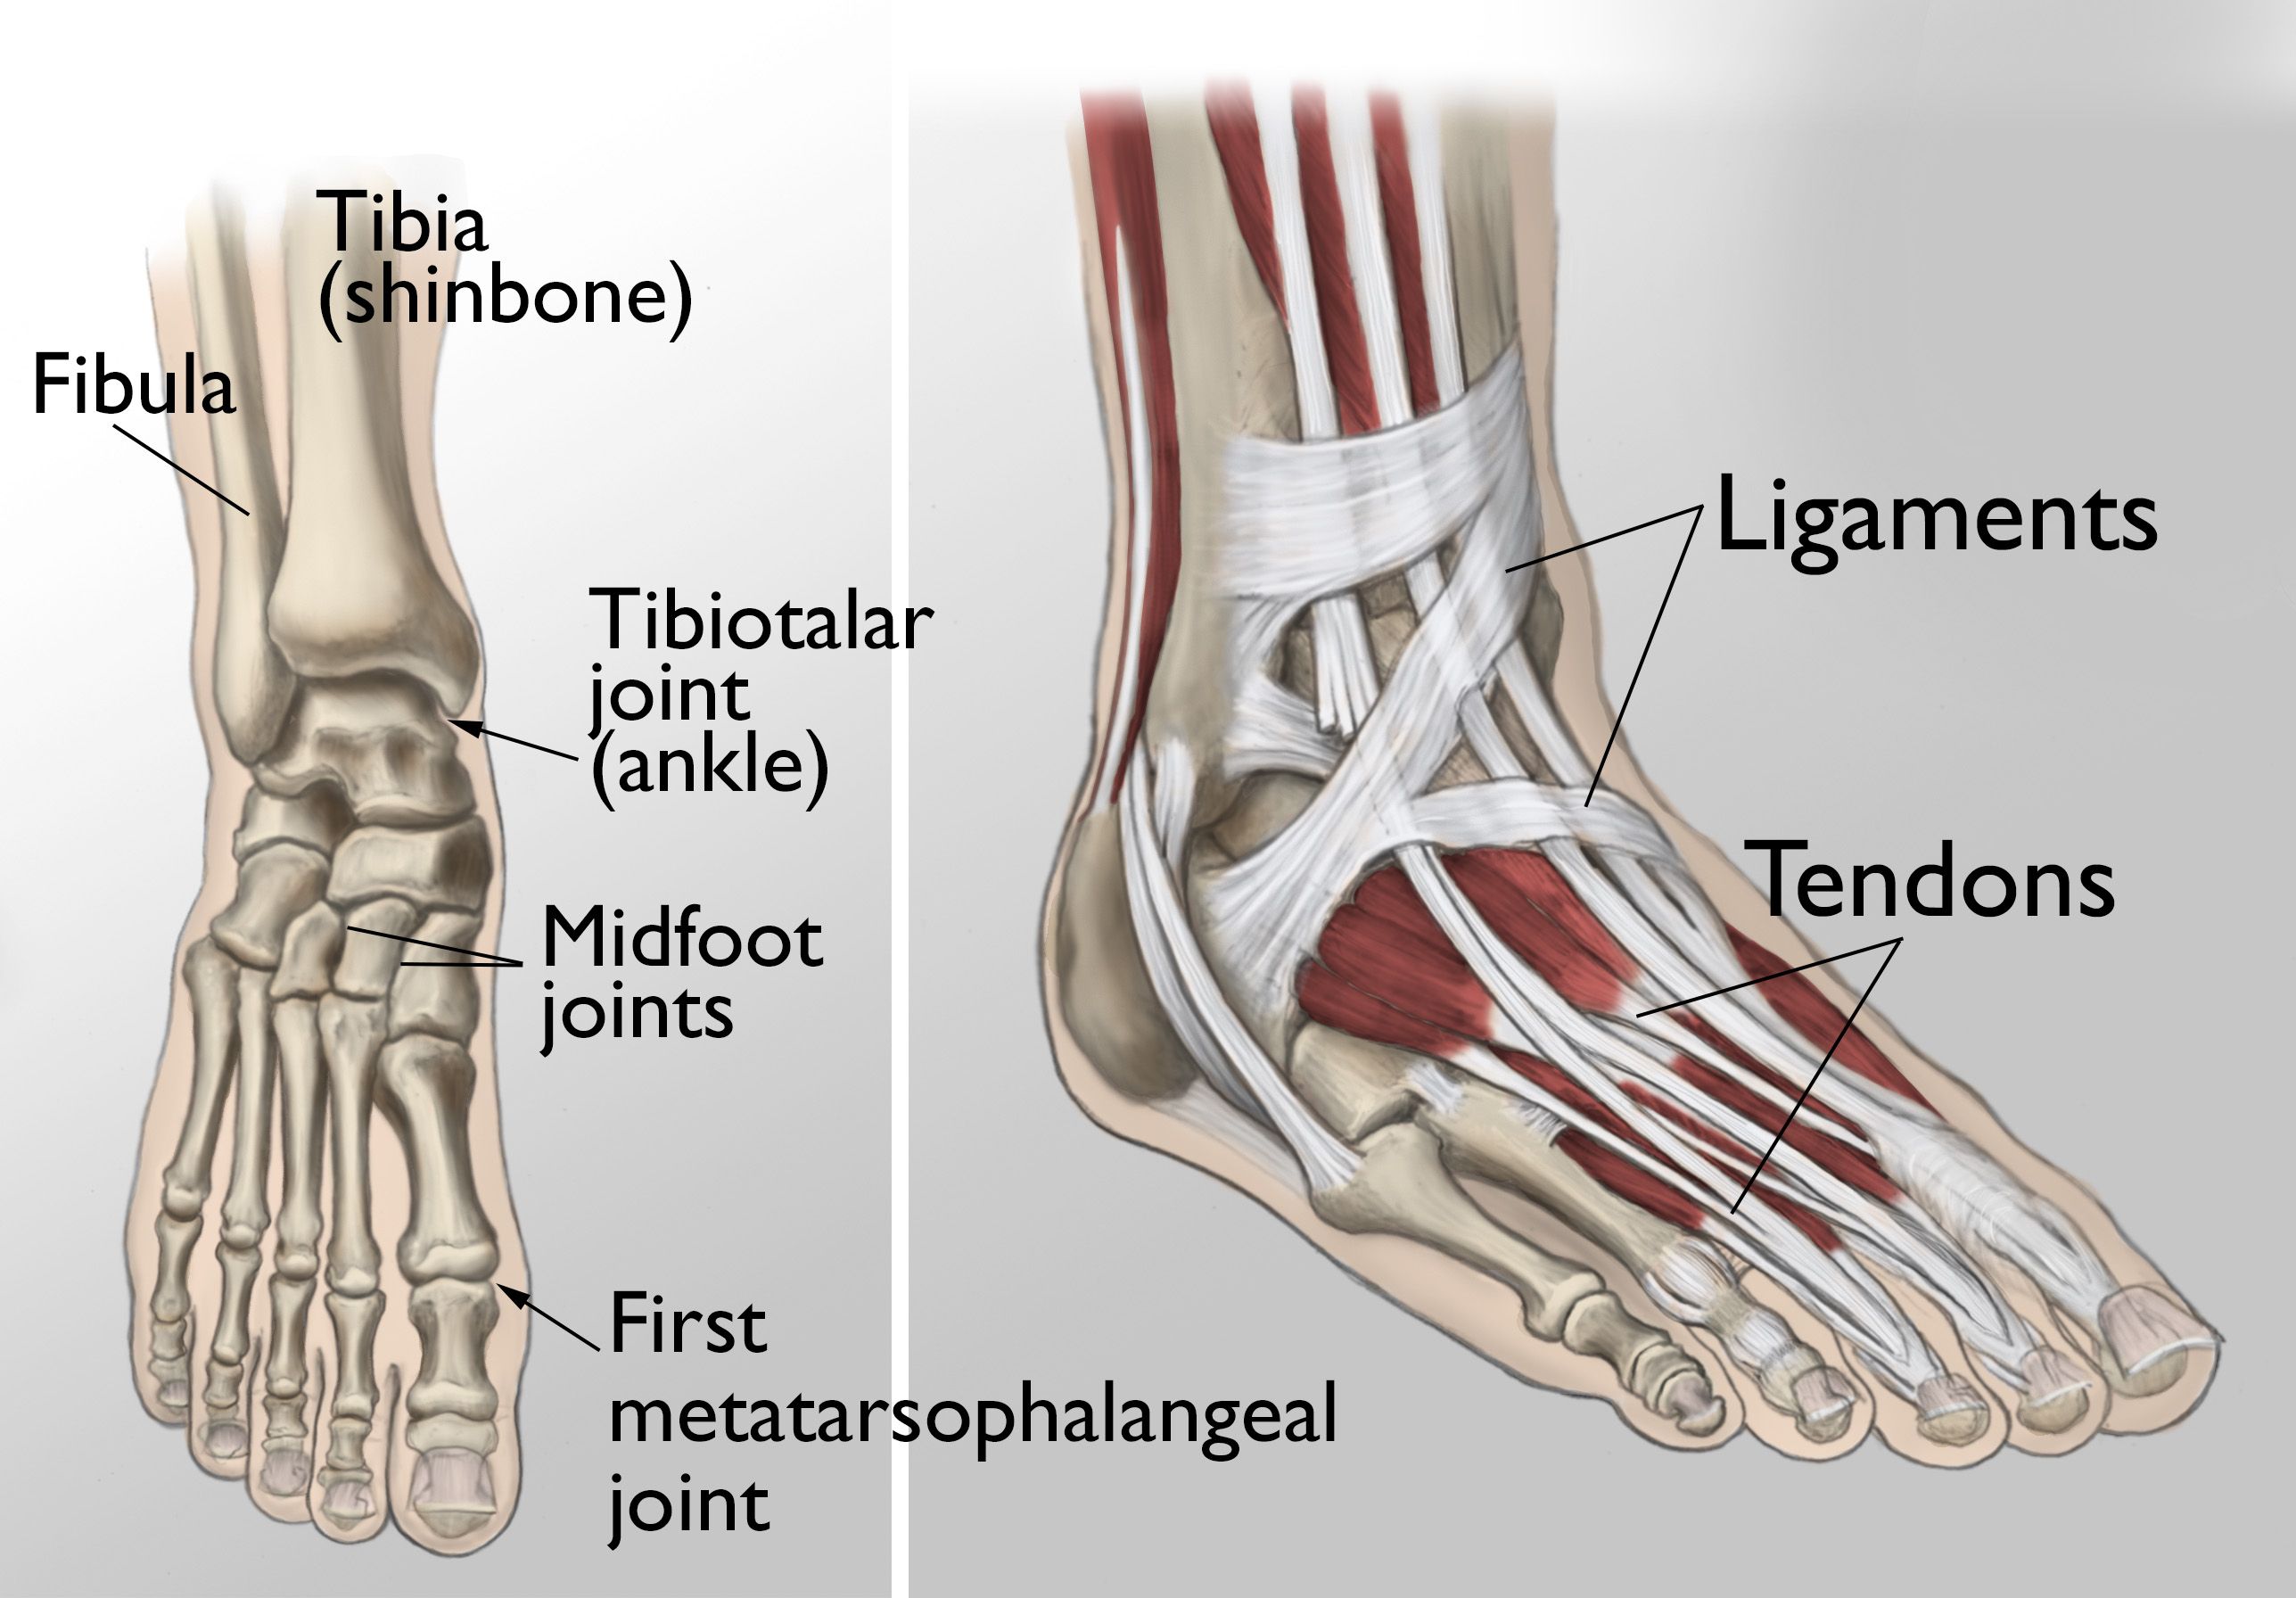

The joints of the ankle, midfoot, and big toe

(Left) The joints of the ankle, midfoot, and big toe are commonly affected by arthritis. (Right) Ligaments connect the bones to each other, and tendons connect the bones to the surrounding muscles of the lower leg.

Reproduced and modified from The Body Almanac. © American Academy of Orthopaedic Surgeons, 2003.

Anatomy

During standing, walking, and running, the foot and ankle provide support, shock absorption, balance, and several other functions that are essential for motion. Three bones make up the ankle joint, primarily enabling up and down movement. There are 28 bones in the foot, and more than 30 joints that allow for a wide range of movement.

In many of these joints, the ends of the bones are covered with articular cartilage — a slippery substance that helps the bones glide smoothly over each other during movement. Joints are surrounded by a thin lining called the synovium. The synovium produces a fluid that lubricates the cartilage and reduces friction.

Tough bands of tissue, called ligaments, connect the bones and provide stability to the joints. Muscles and tendons also support the joints and provide the strength to make them move.